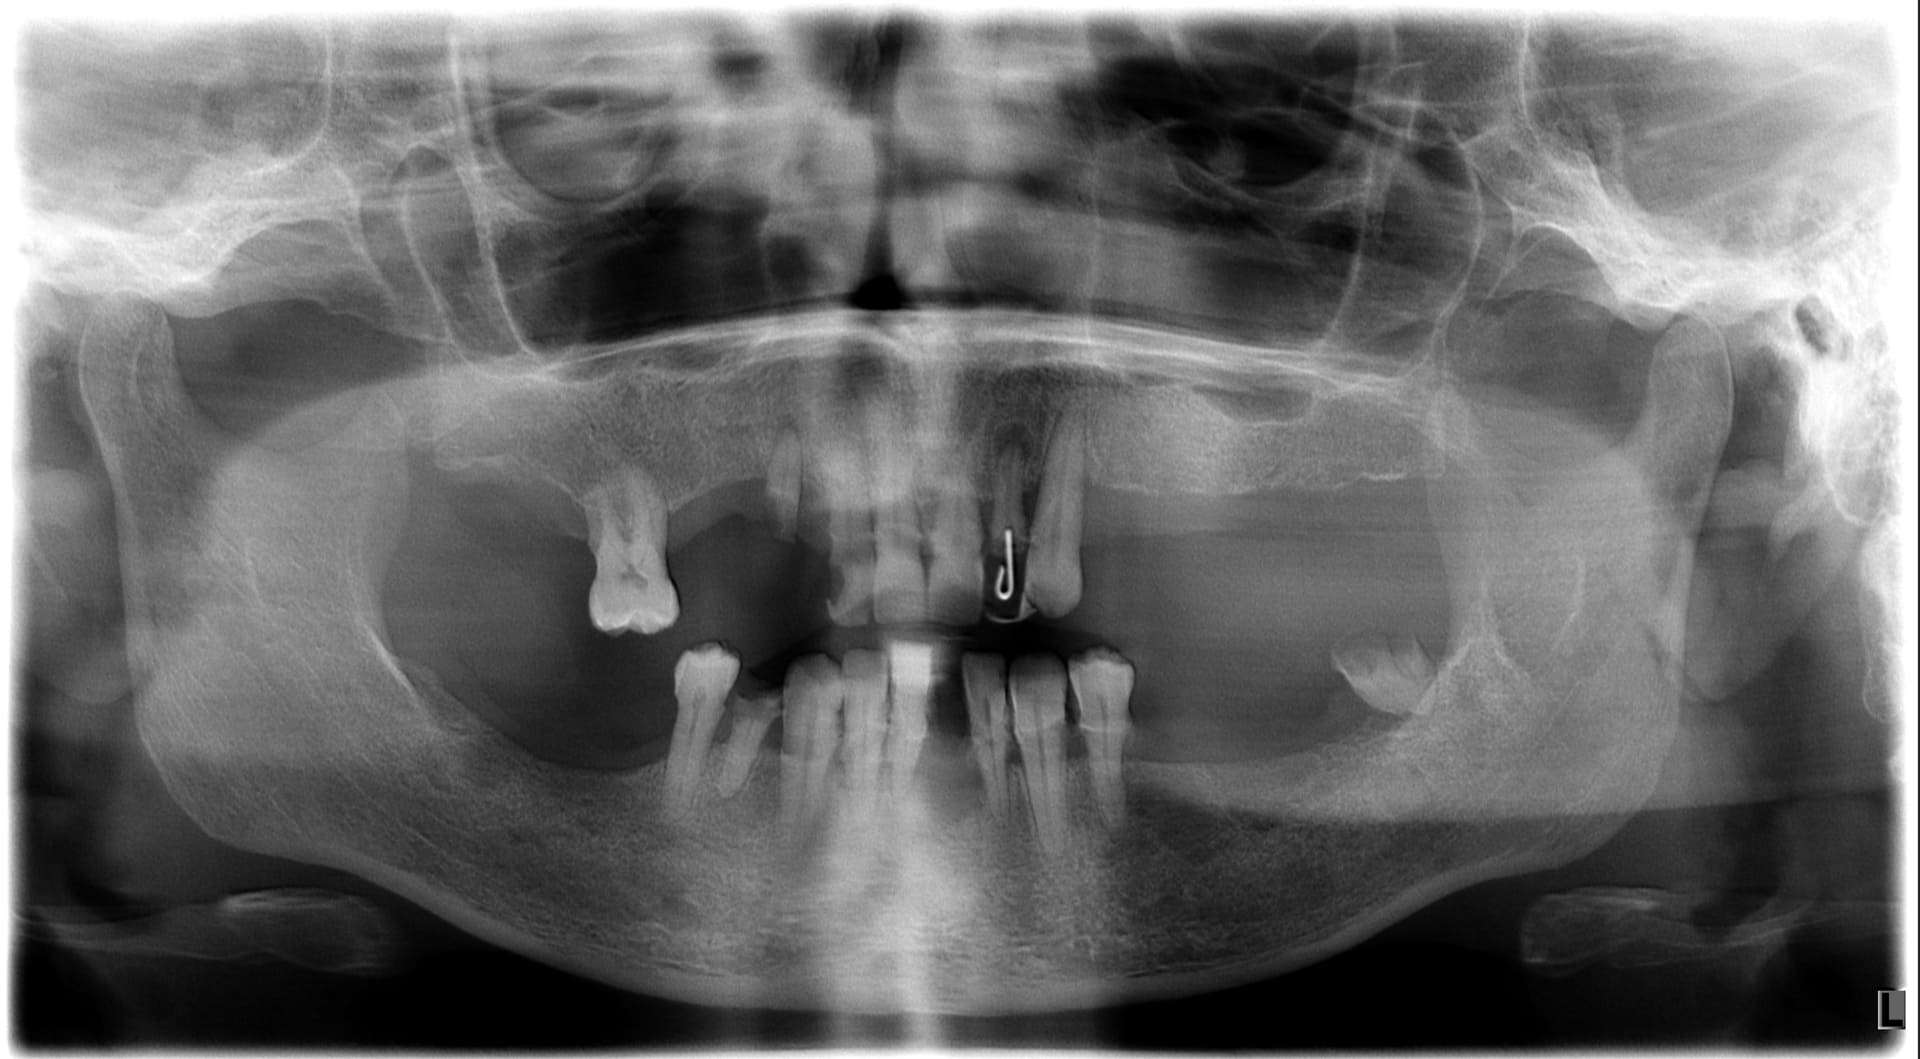

Paziente 1

< Prima